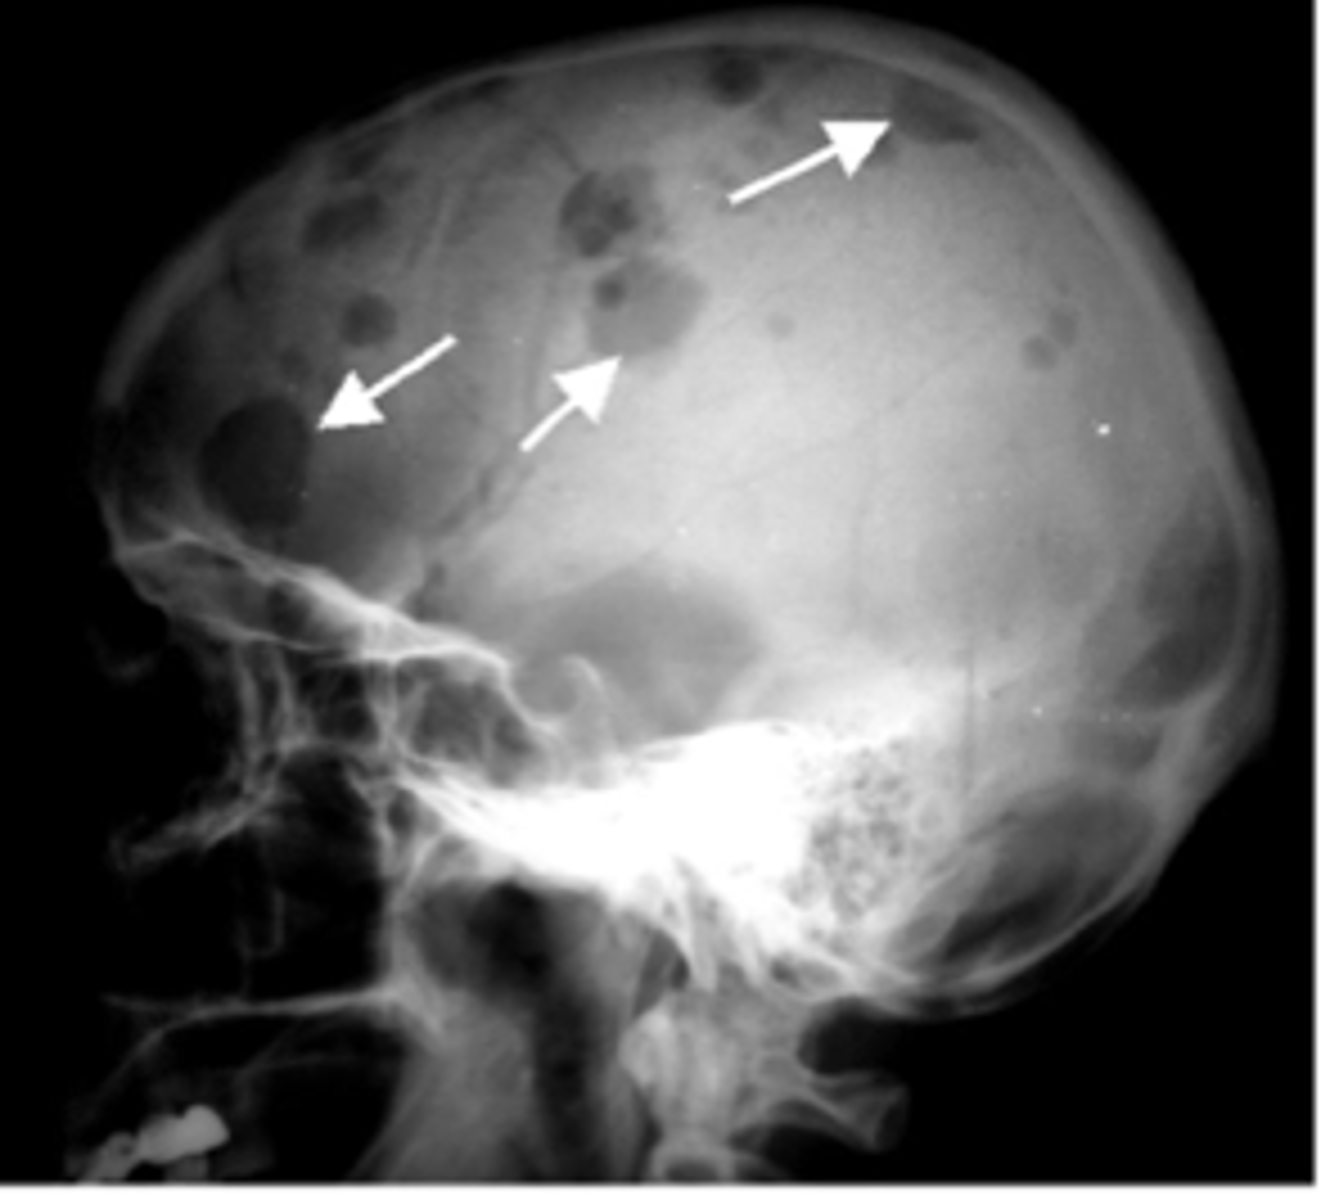

Cerebral leukostasis

Severe headache which can progress to confusion and coma; caused by a WBC clot

Defining characteristics of Multiple Myeloma

High antibody level, osteolytic lesions in bones